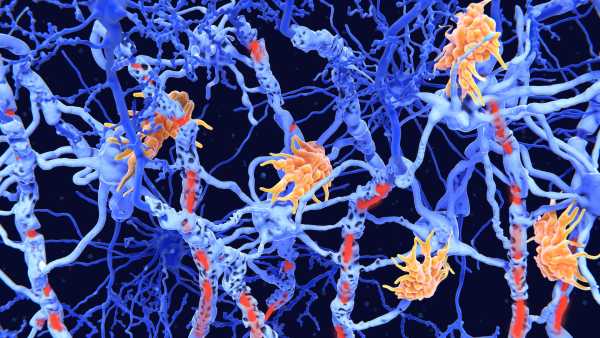

Стикаючись з інфекцією, ці «гуманізовані» миші виробляють імунні клітини, що імітують структуру та різноманітність імунних клітин, що виробляються людьми. Дослідники виявили, що коли їм вводять хімічну речовину, яка викликає поширене запалення в організмі, у мишей розвивається варіант аутоімунного захворювання – вовчака, який дуже схожий на той, що спостерігається у людей.

Після введення людського естрогену миші почали виробляти безліч людських імунних клітин. Серед них були Т-клітини, які безпосередньо атакують мікроби, та В-клітини, що виробляють антитіла, що знищують бактерії та допомагають позначити патогени для знищення.